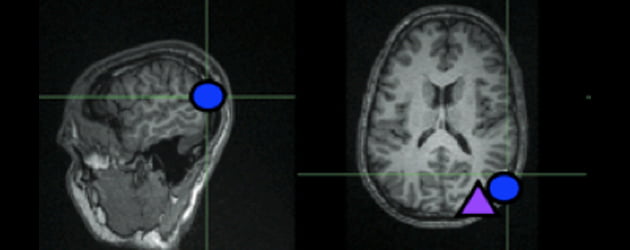

Of we een actie van een ander moreel acceptabel vinden of niet, heeft te maken met een bepaald gebiedje in de hersenen. En door dat gebiedje magnetisch te storen, kun je iemands oordeel beïnvloeden.

Rond deze verhaaltjes werden twee verschillende experimenten uitgevoerd. Bij het eerste werd bij de proefpersonen het hersengebiedje waar het om ging, de rechter temporo-pariëtale junctie (RTPJ), vóór de test 25 minuten lang behandeld met transcraniële magnetische stimulatie (TMS). Bij het tweede kreeg hetzelfde gebiedje een TMS-‘stoot’ van een halve seconde te verstouwen op het moment dat ze een morele beslissing namen.

Beeld: Rebecca Saxe Laboratory/MIT